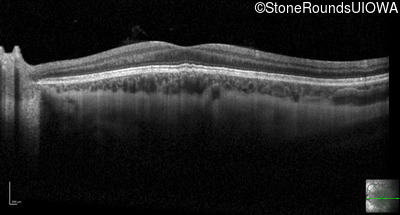

Optical Coherence Tomography - Left - 20/100

Exemplar / OCT Stack

OCT Stack